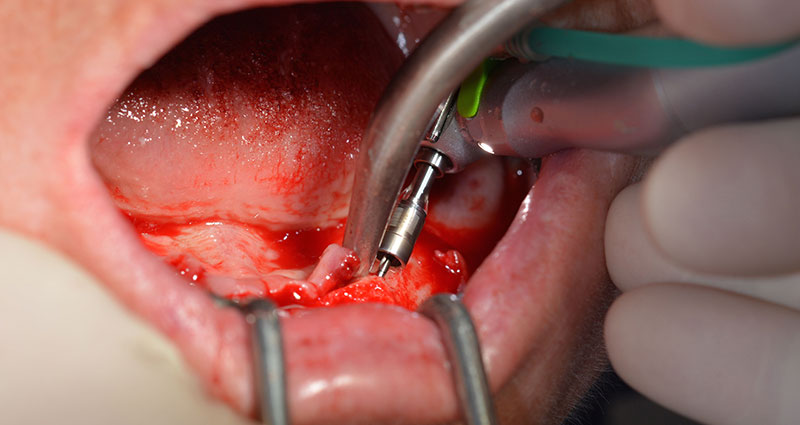

Surgical procedure

After removal of the residual dentition in the mandible, the alveolar crest was exposed from 37 to 47.

The mental foramen was first identified as a limiting anatomical structure and then the cortical bone of the crest was smoothed with the straight handpiece and a large rose-head bur (Fig. 4).